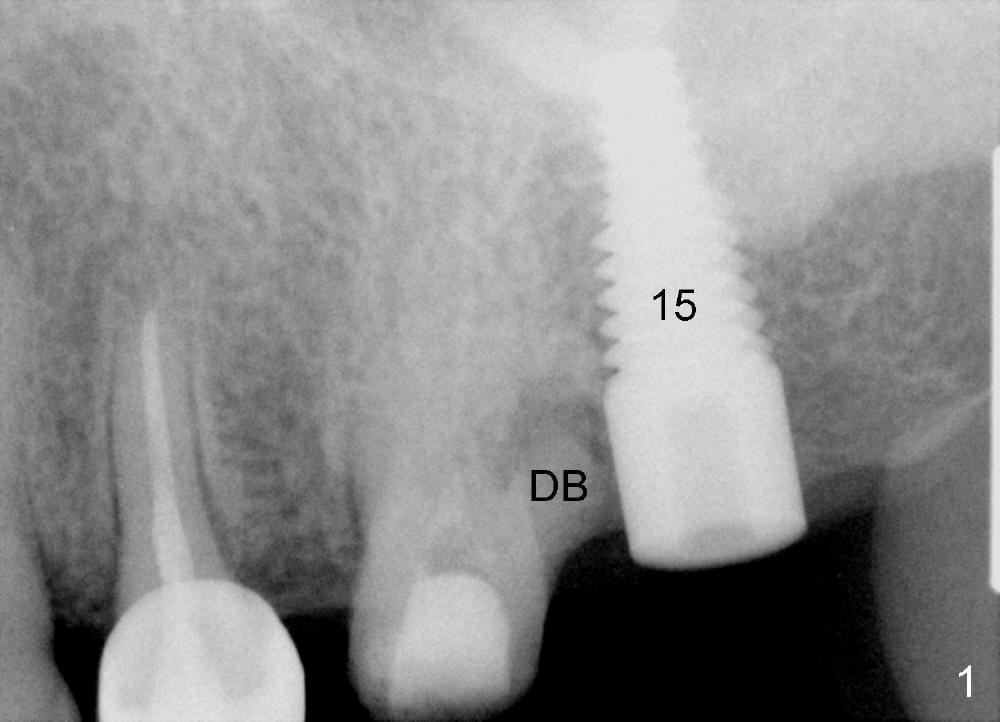

A 50-year-old man has history of a cantilever bridge in the upper left quadrant (from #13 to 15, Fig.1). After bridge removal, a 6x17 mm implant is placed at the site of #15 and root canal therapy is attempted in #14 without success, because of canal obliteration. The tooth is deemed non-salvageable due to the distobuccal root fracture and associated periapical lesion (DB).

The tooth #14 has a large septum, which can hold an implant with diameter of 5 mm (Fig.2, CT axial section). Coronal section shows that the length can be 20 mm (Fig.3).